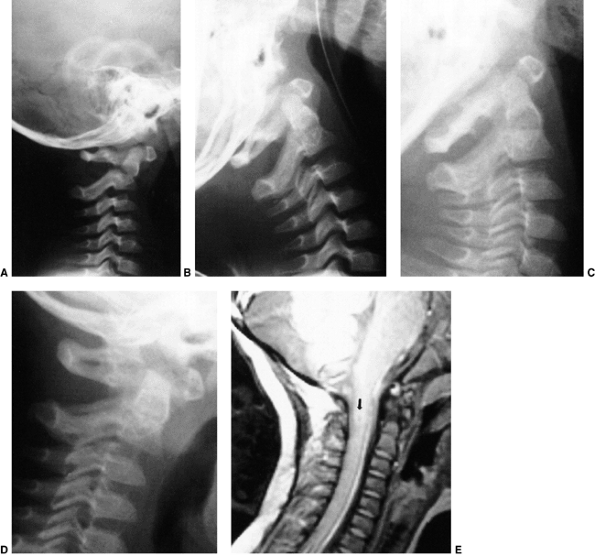

![]() |

Figure 22.14 The child in Figure 22.11

had a fixed deformity that occurred 6 months earlier, immediately after reconstructive maxillofacial surgery for Goldenhar syndrome. It did not respond to traction, including halo traction. She underwent a posterior C1-C2 (Gallie-type) fusion. A solid fusion was present 9 months later; clinically, the patient achieved 80 degrees of rotation to the left and 45 degrees of rotation to the right. |